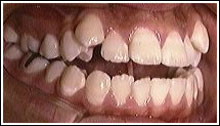

舌小帯と開咬

舌の運動機能障害

症例

永久歯が後ろから!?